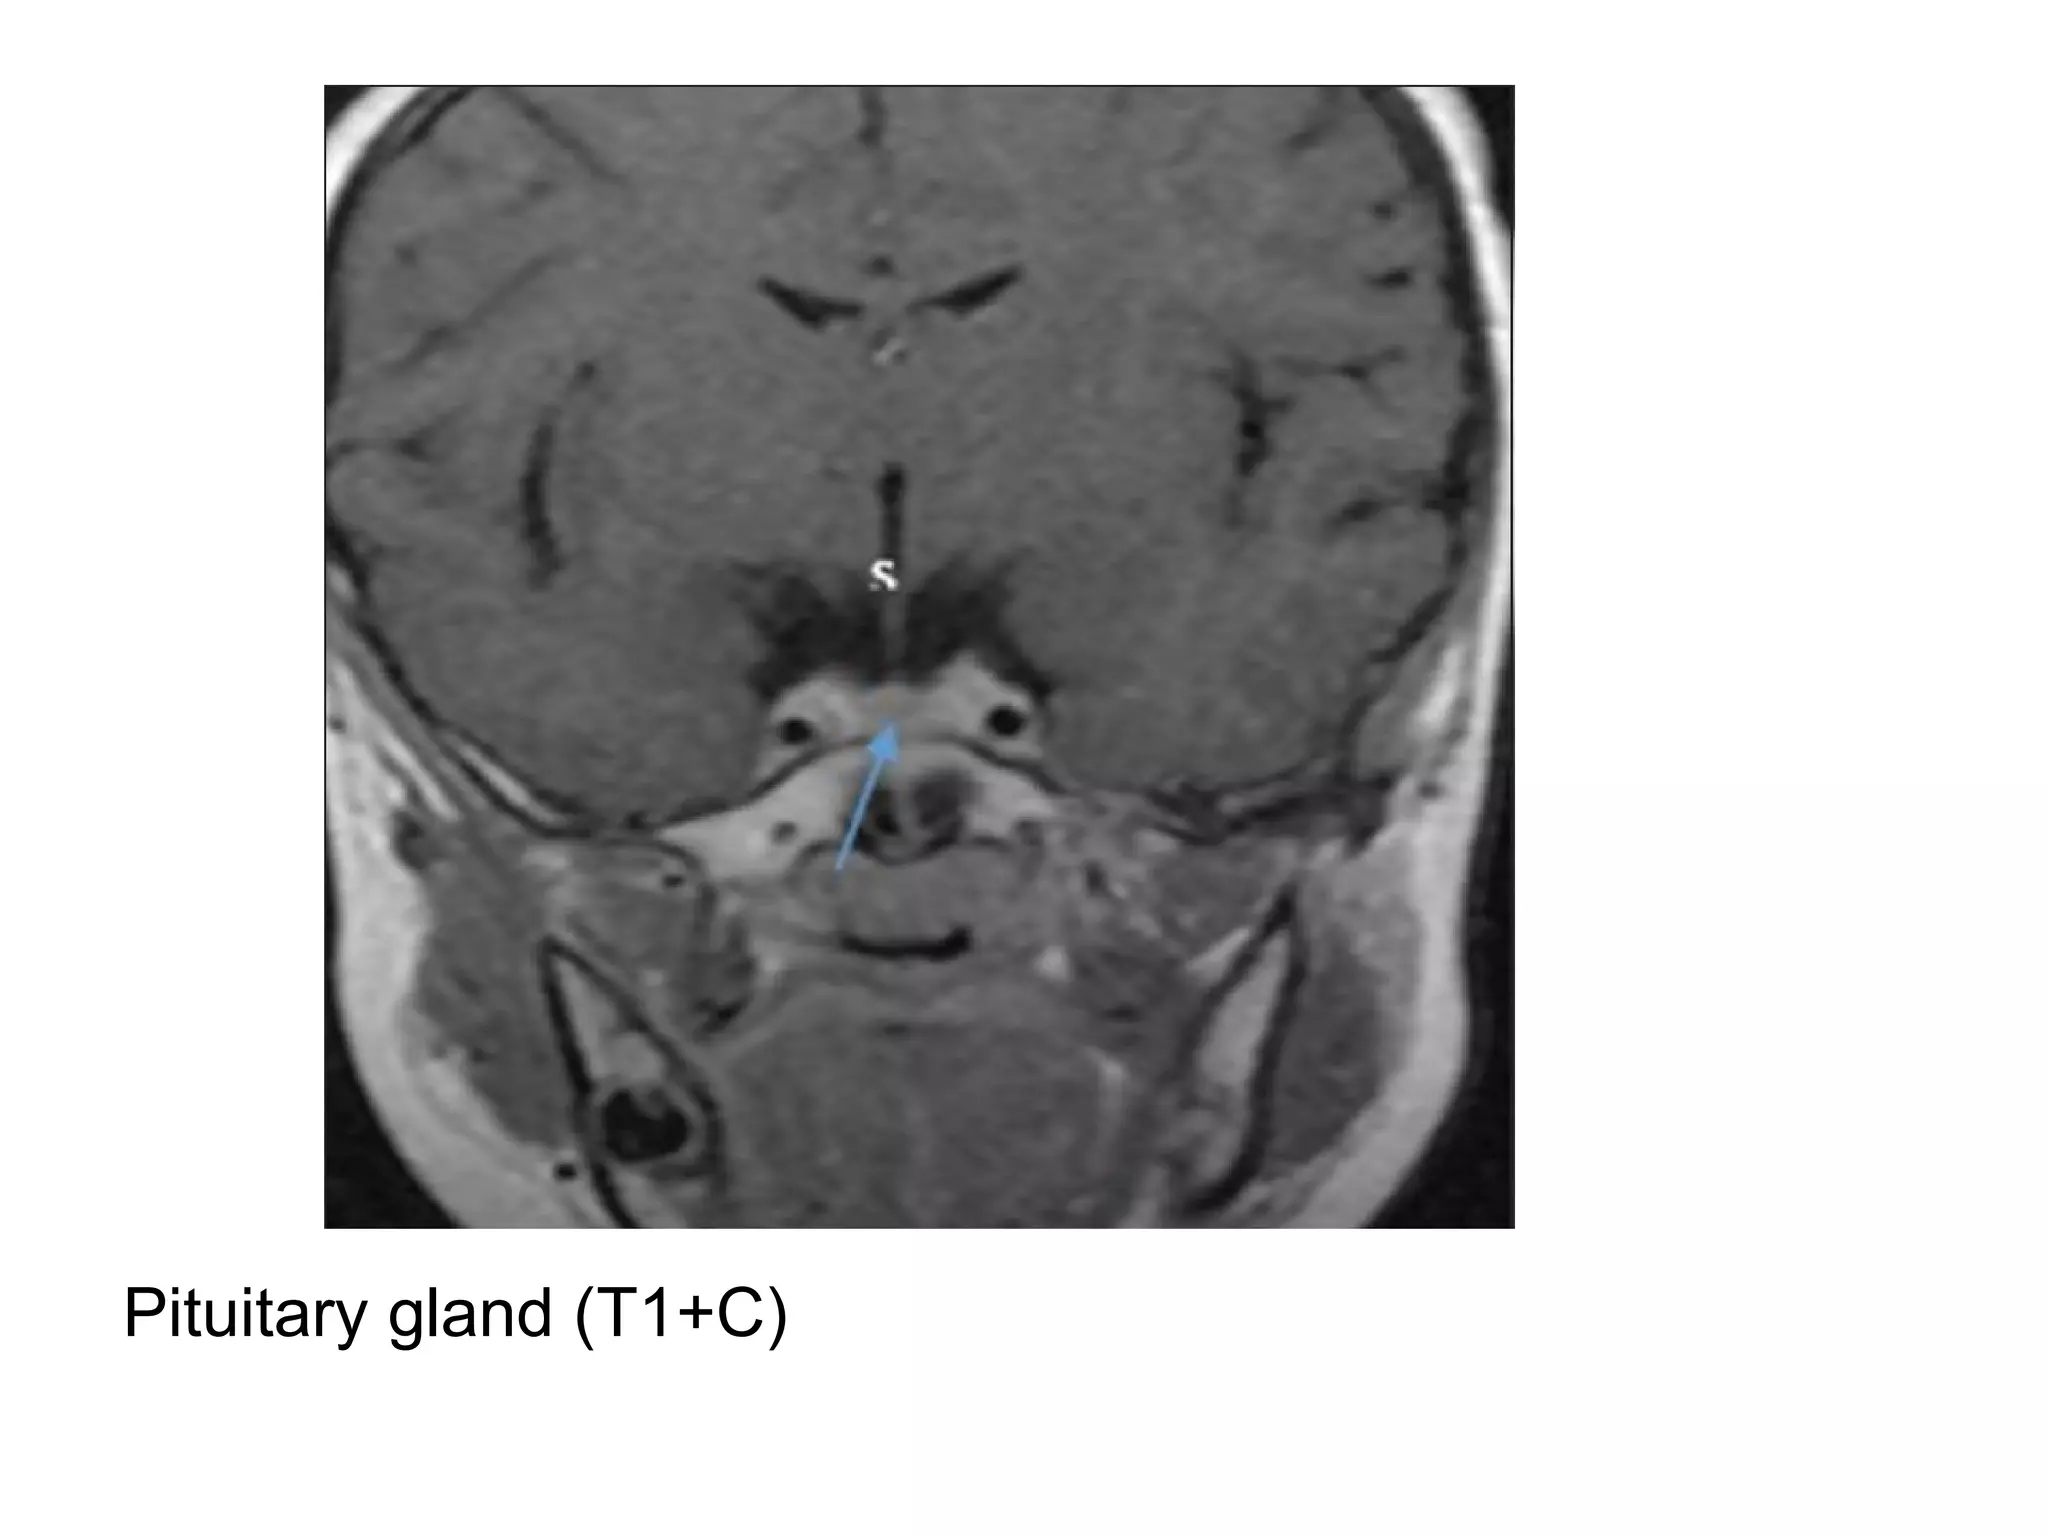

-Several CNS regions don’t have a BBB and therefore

a) Choroid plexus

b) Pituitary & pineal glands

Pituitary gland (T1+C)

-Several CNS regionsdon’t have a BBB and therefore normally enhance : a) Choroid plexus b) Pituitary & pineal glands c) Tuber cinereum (controls circadian rhythm, located in the inferior hypothalamus) d) Area postrema (controls vomiting, located at inferior aspect of the 4th ventricle) -The dura also lacks a BBB , but doesn’t normally enhance -Intracranial enhancement may be intra or extra-axial, extra-axial structures that may enhance in pathologic conditions include the dura (pachymeninges) & arachnoid (leptomeninges)